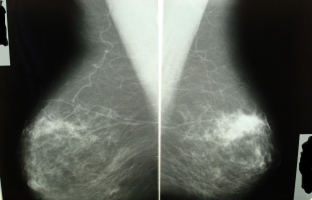

Вузлова мастопатія за формою свого прояву часто схожа на рак молочної залози, і багато онкологів розглядають це захворювання як передпухлинний процес. Щільні вогнищеві утворення при вузловій мастопатії можуть бути одиничними та множинними, визначатися тільки в одній із молочних залоз або виявлятися в обох залозах одночасно. Найчастіше діагноз вузлова мастопатія ставиться жінкам віком від 35 до 45 років, розвиток цього захворювання сильно залежить від гормонального фону і часто активізується при його порушенні, у тому числі через стреси, обмінні порушення в організмі.

Вузлова мастопатія є такими змінами сполучної тканини, при яких утворюються великі кістозні порожнини, проліферація епітелію, сосочкові розростання. Залежно від вираженості процесів форма захворювання може бути проста або проліферуюча. Саме друга форма вузлової мастопатії найчастіше піддається малігнізації і розглядається фахівцями як передраковий стан.

Припустити вузлову мастопатію можна за наявності виділень із соска у поєднанні з чітко пальпованими, чітко обмеженими ущільненнями в грудях. Для вузлової мастопатії характерним є те, що в положенні лежачи ці ущільнення не визначаються. Під час менструації вузлики можуть ставати болючими, напруженими, збільшуватись у розмірах, але це відбувається не завжди.